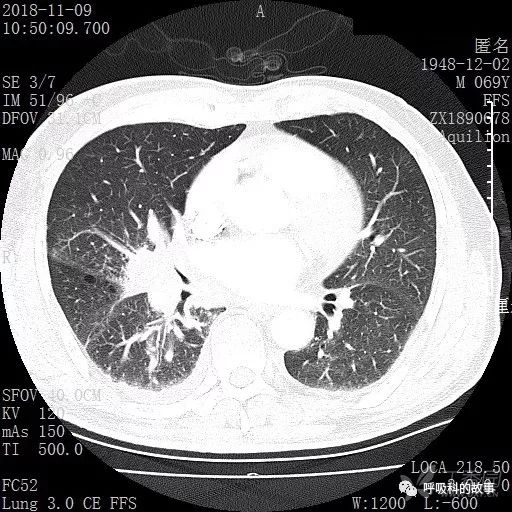

胸部增强CT示右肺门占位伴远端阻塞性肺炎,纵膈、右肺门、右侧颈根部、右侧腋下及肝门部肿大淋巴结。两侧胸腔少量积液。

纵隔窗的增强CT

肺窗CT